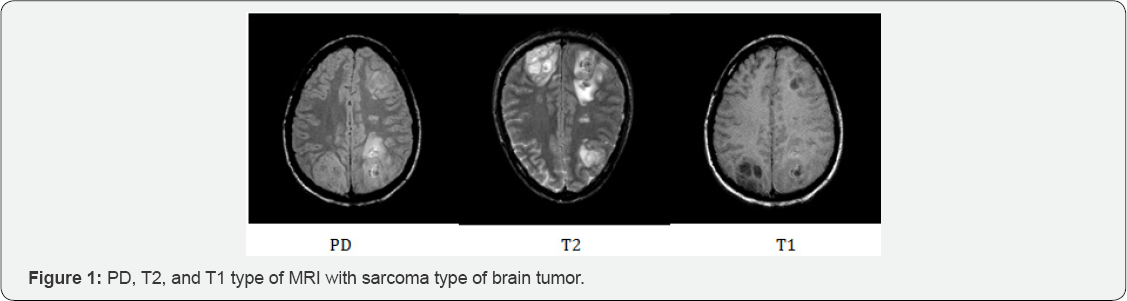

In short, it is stated that the T1 MR images have brighter pixels for white matter (WM), darker for gray matter (GM), and almost black for cerebrospinal fluid (CSF). The T1 images show abnormality with larger intensity value than normal tissue. Therefore, some lesions in the WM areas can look alike GM in T1 images due to the increase of water. Besides, the pixels with muscle tissue appear brighter than for fat. Almost the opposite intensity contrast will be expected in T2 images. The WM is less fluid-based. Thus the pixels with mostly this tissue class will appear white in T1 and dark in T2, which corresponds to high and low-intensity values, respectively. In the case of GM, it appears darker in T1 and brighter in the T2 images. Finally, the CSF shows a small peak but also a big lobe that almost overlaps all the classes. In proton density (PD) images white matter is brighter than gray matter, and gray matter is brighter than CSF. PD, T2, and T1 type of MRI with sarcoma brain abnormality is shown in Figure 1.